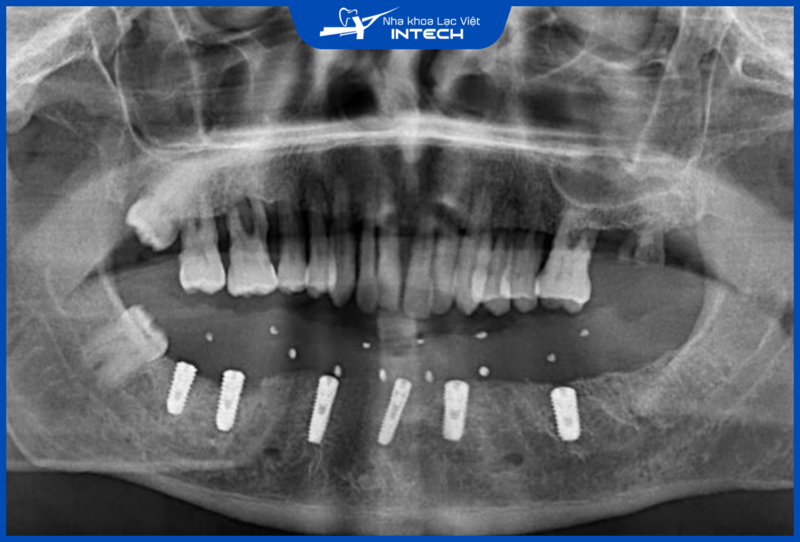

3.4. Đa dạng dòng sản phẩm phù hợp với nhiều trường hợp mất răng

Osstem cung cấp nhiều dòng trụ Implant với hình dáng, kích thước và thiết kế đa dạng, phù hợp với từng nhu cầu phục hình như trồng Implant đơn lẻ, trồng Implant bán hàm hay toàn hàm, đặc biệt là những vị trí hẹp như răng cửa, răng nanh... Sự đa dạng này giúp đảm bảo rằng mỗi khách hàng đều có lựa chọn tối ưu, đáp ứng yêu cầu điều trị lâm sàng cụ thể.